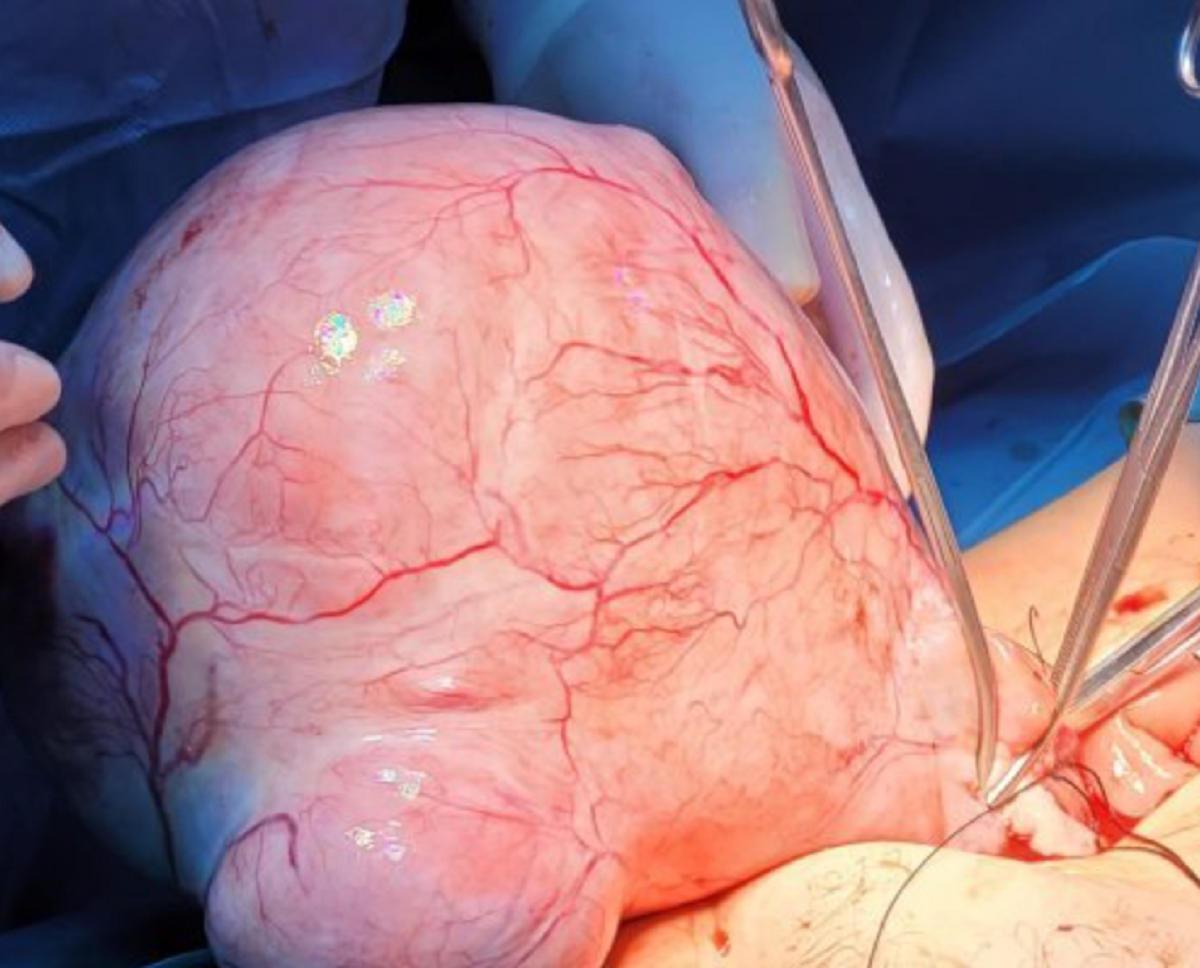

Medicii din Iași s-au confruntat cu un caz rar au operat o pacientă ce s-a prezentat cu o tumoare uterină de 4.300 g și 35 de centimetri diametru.Pacienta în vârstă de 49 de ani a ajuns în stare gravă la unitatea medicală, cu sângerări masive, sindrom anemic sever, cântărind doar 38 de kilograme, informează Ziarul de Iași.

Specialiştii spun că au trecut aproximativ cinci ani de când s-au confruntat ultima dată cu o tumoare de astfel de dimensiuni.

„Pacienta a fost preluată de medicul de gardă din acea zi, dr. Tudor Lazăr. Evaluarea clinică şi paraclinică a evidenţiat o tumoră foarte mare. Ceea ce este particular e că pacienta provine dintr-un mediu socio-economic mai defavorizat, cu handicap psihic sever, s-a prezentat la noi cu însoţitor.

A fost internată iniţial pe ATI având în vedere starea generală, unde s-a instituit un protocol de-al nostru specific de reanimare, inclusiv transfuzii de sânge repetate date fiind anemia ei severă şi particularitatea cazului”, a explicat dr. Ciprian Ilea, medic primar obstetrică-ginecologie şi şeful Secţiei de Ginecologie.

Tumori de astfel de dimensiuni sunt rare

Având în vedere că este un caz foarte rar, a fost instituită o comisia de analiză a cazului, condusă de prof. dr. Bogdan Doroftei, directorul medical al maternităţii, care a decis necesitatea intervenţiei chirurgicale.

A fost necesară o echipă mixtă, din care a făcut parte medicul curant al pacientei, dr. Tudor Lazăr, medic primar obstetrică-ginecologie, dr. Ciprian Ilea, şeful Secţiei de Ginecologie, şi dr. Constantin Condac, şeful Secţiei ATI.

Operaţia de îndepărtare a tumorii a durat aproximativ două ore.

„Intervenţia a avut un grad ridicat de complexitate, astfel de cazuri sunt foarte rare. De obicei se întâlnesc la paciente care nu sunt investigate o perioadă lungă, iar în cazul său evoluţia putea fi fatală, dacă nu ajungea la timp era destul de probabil să nu poată ajunge deloc”, a completat medicul ieşean.

Medicii spun că evoluţia post operatorie a pacientei este favorabilă, însă este nevoie să fie monitorizată în continuare, existând riscul de apariţie a unor complicaţii.

Va mai rămâne internată în spital pentru cel puţin cinci zile şi va trebui să vină constant la controale. De asemenea, asistentul social din spital va lua legătura cu cel din comuna din care provine femeia pentru a putea fi monitorizată corespunzător, în special în legătură cu starea generală de nutriţie.

„La noi nu a mai fost de foarte mult timp un astfel de caz, mai ales în care pacienta să nu ştie. A mai fost un caz cu o tumoră de 4.500 de grame, dar în urmă cu 4-5 ani”, a mai spus dr. Ciprian Ilea.